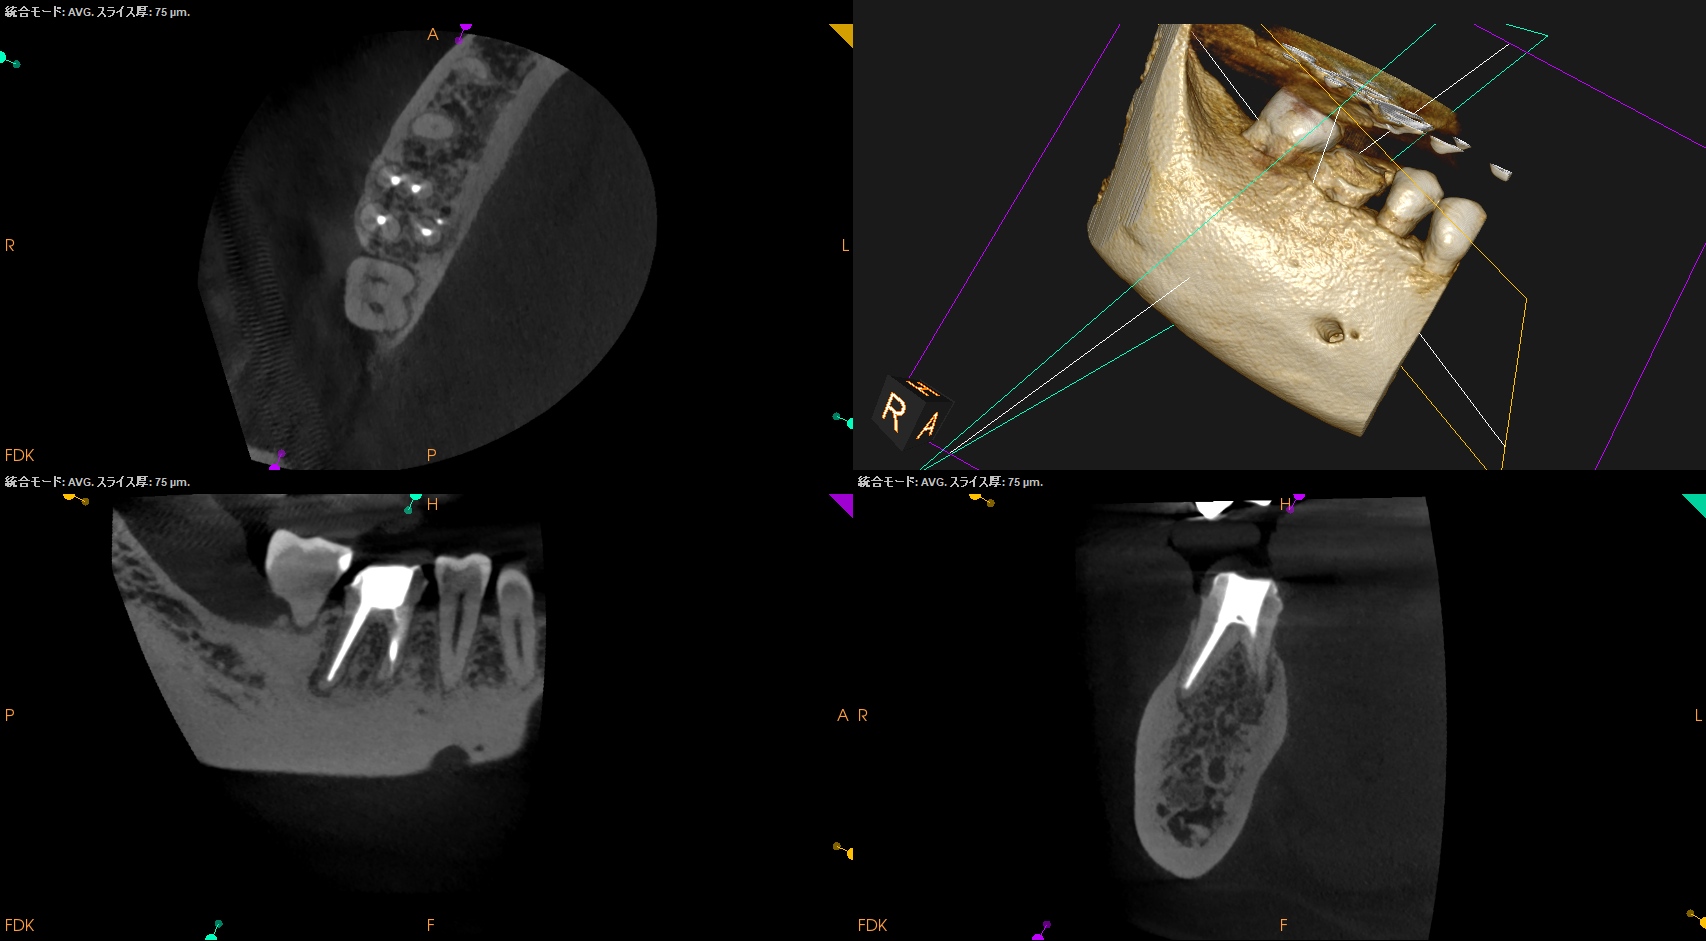

#30 Re-RCT 1yr recall(2026.3.10)

MB

ML

D

Radix

初診時と比較した。

病変は完治した。

このことから最終補綴もOKだし、経過観察も終診とさせていただいた。